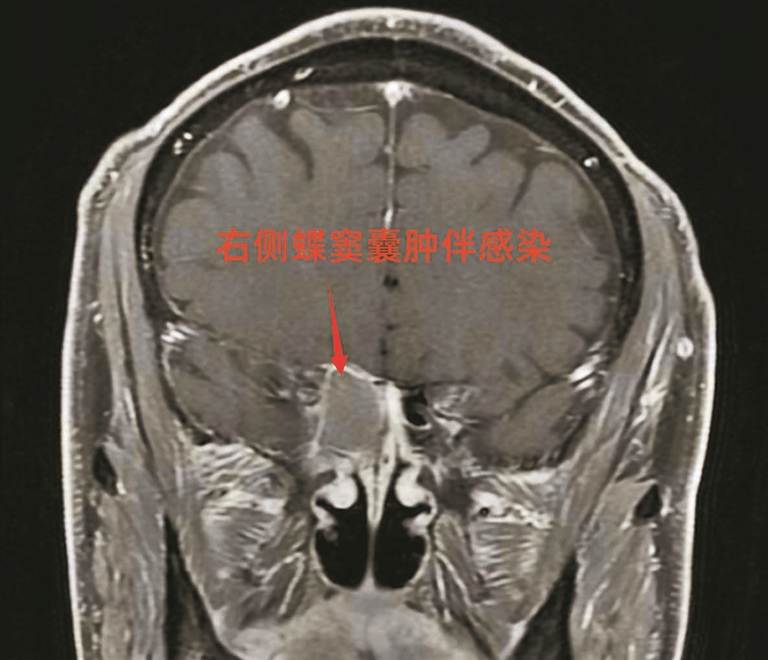

老田核磁檢查發(fā)現(xiàn)蝶竇囊腫。

住院后,楊成明立即為老田安排了頭顱核磁共振、頸動脈彩超等關(guān)鍵檢查。次日結(jié)果提示:蝶竇內(nèi)有一個30mm×20mm的囊腫。蝶竇位于鼻腔深處、顱底位置,緊鄰視神經(jīng)。

經(jīng)耳鼻喉科進一步檢查,確認右側(cè)蝶竇囊腫嚴(yán)重壓迫視神經(jīng),這正是其視力驟降的主要原因。